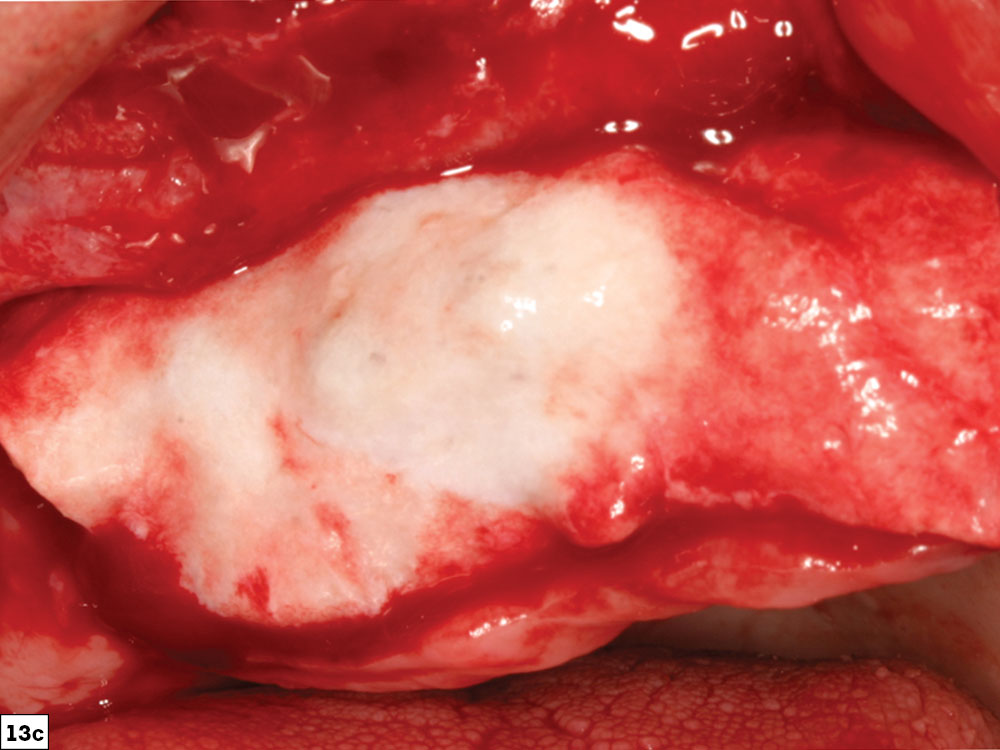

Barrier membranes in GBR procedures are usually classified as either resorbable or non-resorbable. Resorbable membranes (e.g., collagen) are the most commonly used membranes for GBR techniques. Resorbable membranes are cost-effective, easy to use and naturally biodegradable, and have varying resorption rates. For ridge augmentation procedures, a longer-acting collagen barrier such as the Newport Biologics Resorbable Collagen Membrane 4–6 (Glidewell) is recommended. These cross-linked membranes are ideal for containing the graft, especially for grafts that require longer healing periods (Figs. 13a–13c).

Guided Bone Regeneration: 8 Steps to Successful Ridge Augmentation Fig. 13a CSM v15I2

Guided Bone Regeneration: 8 Steps to Successful Ridge Augmentation Fig. 13b CSM v15I2

Guided Bone Regeneration: 8 Steps to Successful Ridge Augmentation Fig. 13c CSM v15I2

Figures 13a–13c: Newport Biologics Resorbable Collagen Membrane 4–6 (13a); maxillary anterior graft site (13b); collagen membrane positioned over graft site (13c).